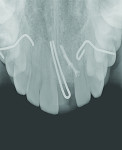

After 11 years, at 17 years of age, the patient expressed interest in a definitive treatment plan to address the associated increased mobility and short clinical crown length of the left maxillary incisor. The clinical examination revealed compromised gingival architecture in disharmony with adjacent teeth, an incisal edge position apical to the incisal edge position of the maxillary right central incisor, and a reduced anteroposterior ridge (Figure 1). The radiographic examination revealed severe root replacement resorption (Figure 2). Treatment options discussed included extraction of the left maxillary incisor followed by placement of a removable and fixed-tooth or implant-supported restoration. A staged treatment approach to maximize esthetic and functional treatment outcome with surgical soft- and hard-tissue augmentation procedures was also discussed with patient and parent but was declined. The patient elected to proceed with extraction of the unsalvageable left maxillary incisor and placement of an immediate provisional removable partial denture.

The clinical crown and the remaining gutta percha material were extracted atraumatically by forceps technique followed by immediate placement of an endosseous implant—a 3.3-mm diameter regular neck (RN) 14-mm implant (Straumann AG, www.straumann.com) in the left maxillary central incisor area (Figure 3).

The analysis of the radiographs after the first implantation and after implant fracture (Figure 3 and Figure 7) demonstrates that bone loss of about 1.4 mm occurred in the maxillary implant area. The implant fractured at the base of the osseous defect, where one loss might have made the thin implant more fracture-susceptible.